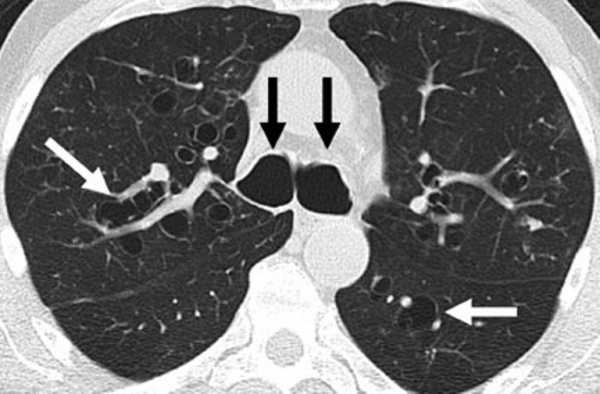

КТ легких. Расширенные бронхи (черные стрелки) и бронхоэктазы (белые стрелки).

- Рентгеновская диагностика.Обзорная рентгенография легких выявляет вторичные изменения в легочной паренхиме, резко расширенную трахею, диаметр которой шире диаметра позвоночного столба. Для уточнения состояния ТБД и распространенности поражения выполняется бронхография. Более точную рентгенологическую картину получают с помощью КТ легких, по данным которой обнаруживается аномальное расширение дыхательных путей (диаметр трахеи >25-27 мм у мужчин и 21-23 мм у женщин).